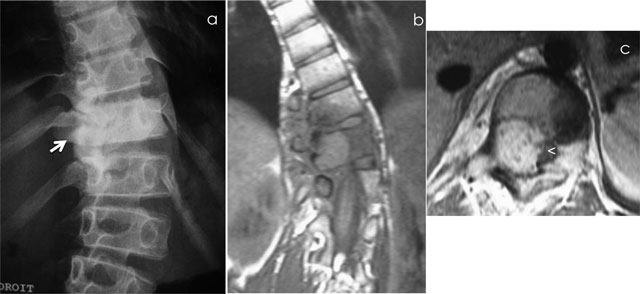

Figure 3

Osteoblastoma of T11. Radiograph (a) shows scoliosis and focal sclerosis of T11 (arrow). Coronal T1-WI (b) and axial T1-WI after gadolinium contrast administration (c) shows a lesion of the neural arch of T11, intralesional calcification and adjacent bone marrow edema of the vertebral bodies of T10 and T11. Note the compression of spinal cord (arrowhead).